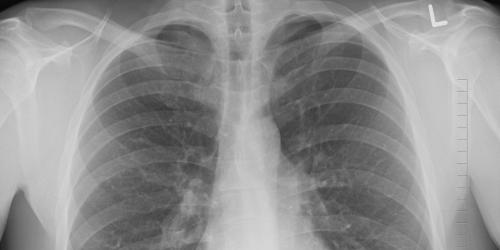

Kontaktpersonen werden in das Gesundheitsamt vorgeladen und, falls notwendig, entsprechende Untersuchungen angeordnet. Zum Ausschluss oder Nachweis einer Infektion führt das Gesundheitsamt Untersuchungen (Bluttestung, Röntgen-Diagnostik, Sputum-Untersuchung) durch.

Personen, die in einer Gemeinschaftsunterkunft (Obdachlose, Flüchtlinge) aufgenommen werden, müssen den Nachweis erbringen, dass keine ansteckende Lungentuberkulose bei ihnen vorliegt. Diesen stellt das Gesundheitsamt nach erfolgter Untersuchung aus.